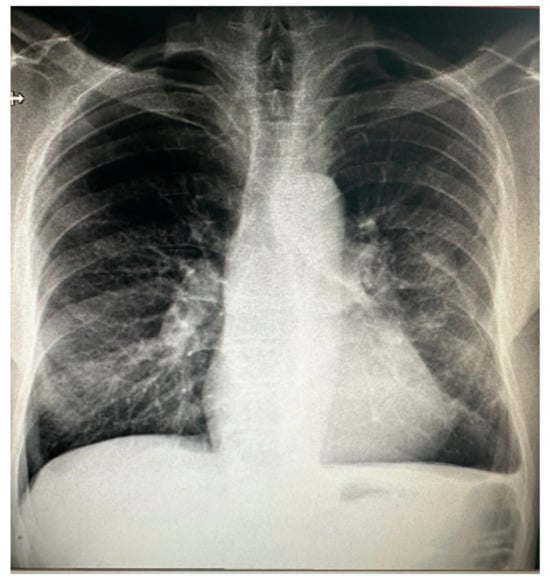

2. Case Report